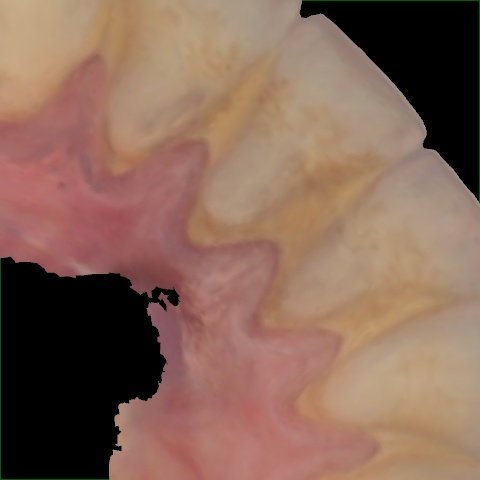

Annotated as "Good"